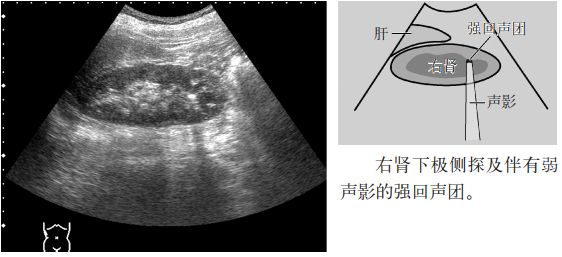

图3 肾结石

注意:小于5mm的肾结石几乎无声影,但是,超声入射角度微妙的变化可以显示点状高回声和声影。因此,平静呼吸时或改变经肋间扫查的位置,有时会出现声影,因此,不仅要在吸气时观察,还应在呼气时或改变经肋间扫查的位置时进行观察。